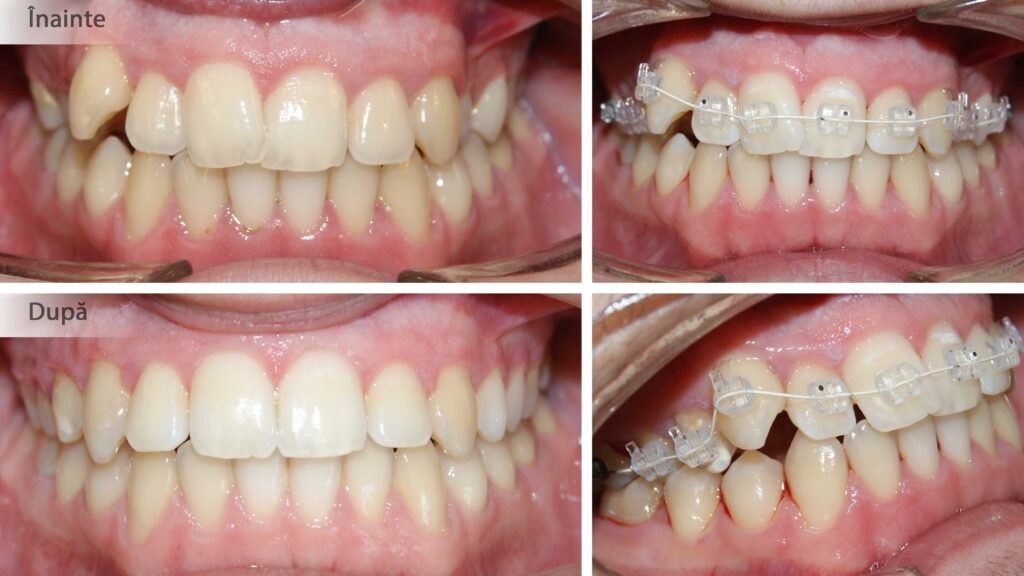

Crearea spațiului pentru alinierea dinților și pentru corectarea mușcăturii încrucișate.